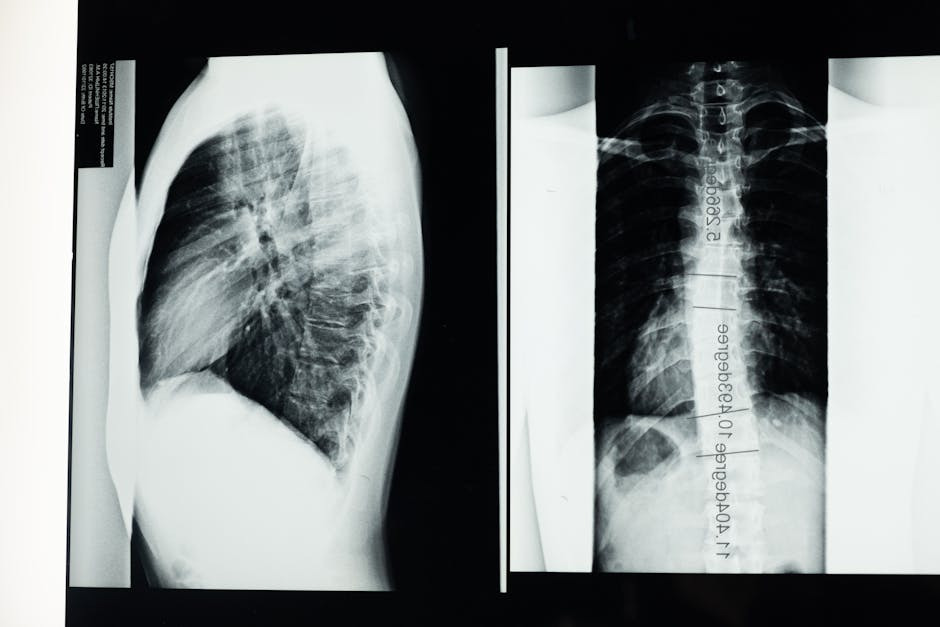

그러면 우리 몸은 척추뼈가 몇개일까요? 경추(Cervical)7개, 흉추(Thoracic) 12개, 요추(Lumbar) 5개, 천추 (엉치뼈) (Sacrum ) 5개, 미추Coccyx (3~7개), 총 33개의 뼈로 구성되어 있습니다. 사람에 따라서 척추뼈 갯수가 적거나 더 많을 수도 있습니다. 앞에서 척추를 보면 일자, 옆에서 보면 완만한 S자로 되어있습니다.

X-ray 검사

척추측만증을 진단하는 가장 일반적인 방법은 X-ray 촬영입니다. 의사는 환자의 측면 사진과 전후 사진을 통해 척추의 각도를 측정하고 평가합니다. 이를 통해 휘어진 정도와 위치를 정확히 파악할 수 있어 적절한 치료 계획을 세우는 데 중요한 역할을 합니다.